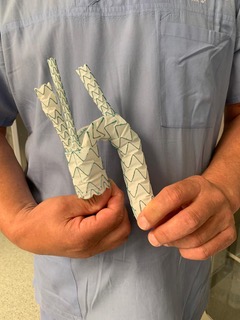

2022-11-07Lekarze Kliniki Chirurgii Naczyniowej, Ogólnej i Angiologii naszego szpitala dokonali pierwszego w kraju, całkowicie przezskórnego wszczepienia modyfikowanego stent-graftu. Była to operacja ratująca życie, a pomocna przy tym - technika druku 3D.

Dostępy całkowicie przezskórne (bez cięcia skóry) wykonuje tylko kilka ośrodków w Polsce i jest to metoda coraz częściej preferowana, ale głównie do mniej skomplikowanych przypadków. Tym razem do szpitala na Pomorzanach trafił 75-letni pacjent z objawowym tętniakiem okołotrzewnym (aorty piersiowo-brzusznej) - bolesnym, grożącym pęknięciem, a zatem stanowiącym zagrożenie życia. Dodatkowo chory nie miał szans na skorzystanie ze standardowego stent-graftu branchowego (z doszywanymi „rękawkami” na naczynia) czy fenestrowanego (z wyciętymi „okienkami” na naczynia) zamawianego u producenta z powodu występujących u niego dodatkowych naczyń, odchodzących od aorty (osobne ujście tętnicy wątrobowej). Nie mógł też czekać na wyprodukowanie stent-graftu szytego dla niego na miarę, bo trwałoby to 8-12 tygodni, a bolesność tętnika świadczyła, że rychło pęknie. Groziło to śmiercią pacjenta.

Leczenie stent-graftami modyfikowanymi jest w domeną naszych lekarzy Kliniki Chirurgii Naczyniowej, Ogólnej i Angiologii, którzy wypracowali wysokiej jakości standard postępowania w użyciu tej metody. Wykorzystując model aorty danego pacjenta, wydrukowany techniką 3D, modyfikują własnoręcznie, już na sali operacyjnej standardowe stent-grafty i dopasowują je indywidualnie do anatomii operowanego pacjenta. Po co? Bo mimo ogólnej takiej samej budowy każdego z nas, układ naczyń krwionośnych, ich budowa, odległości między poszczególnymi naczyniami różnią się u każdego człowieka. Dlatego dla efektywności działania wszczepianego, standardowego stent-graftu – proteza ta powinna być dopasowana do budowy chorego. Chirurdzy naczyniowi USK-2 są jedynym zespołem w Polsce, który tego typu zabiegi wykonuje rutynowo, również w przypadkach nagłych. Jednak taki sposób leczenia, jak i wszelkie inne zaawansowane procedury aortalne, wymaga licznych, często trudnych dostępów naczyniowych (np. nacięć w pachwinach, rękach i klatce piersiowej) – tj. cięć i operowania „na otwarto”. Dla chirurga taka operacja jest łatwiejsza, bo pole operacyjne jest widoczne jak na dłoni. Ale dla pacjenta dochodzenia do formy po takiej operacji jest długotrwałe, bolesne i mało komfortowe. Dlatego użycie przez szczecińskich lekarzy wyłącznie dostępu przezskórnego (bez cięcia) w leczeniu tętnika jest dużym krokiem na przód w chirurgii naczyniowej, a fakt, że to pierwszy tego typu zabieg w Polsce to ogromny sukces naszych „naczyniowców” i świadczy o ich doskonałej technice operowania.

„Modyfikacja stent-grafu naszą, ‘szczecińską metodą’ pozwoliła na pokonanie technicznych trudności, dostosowanie protezy do chorego i wykonanie zabiegu „od ręki”. Zastosowaliśmy modyfikację stent-graftu z okienkami na cztery naczynia trzewne - mówi dr hab. n. med. Arkadiusz Kazimierczak, który wraz z dr. n. med. Pawłem Rynio operował mężczyznę. „Wykonanie przezskórne - dwa dostępy do tętnicy podobojczykowej na klatce piersiowej i obu udowych w pachwinach, zamiast jak dotychczas czterech - pozwoliło na zminimalizowanie urazu operacyjnego tak, że chory był w pełni uruchomiony już w pierwszej dobie po zabiegu i zapytał o termin wypisu ze szpitala – dodaje dr Paweł Rynio. Operacja odbyła się 20 września.

Obaj lekarze są członkami szczecińskiego Aortic Teamu, zespołu chirurgów naczyniowych i kardiochirurgów stosujących nowatorskie metody leczenia w przypadku tętniaków. Zespół planuje rozszerzenie wskazań do zabiegów całkowicie przezskórnych w leczeniu patologii łuku aorty. Pierwsze próby z ograniczeniem urazu operacyjnego w tym zakresie zostały już podjęte w przypadku innej operowanej chorej. Tym razem zastosowano dwa małe cięcia przy wymianie całego łuku aorty, zamiast jak dotychczas pięciu. Pacjentka również jest w dobrym stanie.

Tłumacząc obrazowo - tętniakiem aorty nazywany nadmierne (o ponad 50%) poszerzenie aorty, która jest największą tętnicą w ciele człowieka. Może ono występować na każdym jej odcinku, ale najczęściej występuje w części brzusznej. Przyczyną ich powstania jest odkładanie się blaszek miażdżycowych, nadciśnienie tętnicze, nadmierny, gwałtowny wysiłek czy uraz, czasem także wrodzone nieprawidłowości w budowie naczynia. Ryzyko wystąpienie tętniaka aorty brzusznej wzrasta z wiekiem i jest szczególnie wysokie u mężczyzn około 65. roku życia. Szczególnie niebezpieczne są tętniaki bezobjawowe, które w każdej chwili mogą grozić pęknięciem i prowadzić do zgonu chorego.